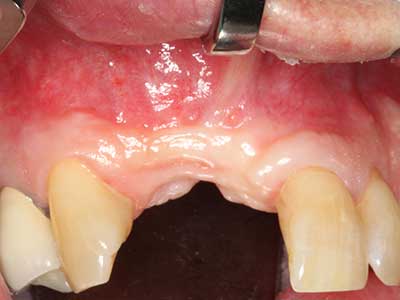

En pacientes de edad avanzada, las enfermedades periodontales marginales representan la razón principal por la que es preciso realizar una extracción. Estas enfermedades tienen principalmente su causa en una colonización bacteriana de la bolsa periodontal y en la inflamación que esta provoca, lo que da lugar a una pérdida del ligamento periodontal. La formación de biopelículas y concreciones subgingivales representa un factor etiológico decisivo para la degradación ósea marginal, por lo que su eliminación cobra una importancia especial en la terapia (Drisko 2014, Plessas 2014).

En el tratamiento de una periodontitis se hace una diferenciación entre la fase inicial y la fase quirúrgica. Además de la instrucción y la motivación entorno a la higiene bucal, en ambas fases debe realizarse una limpieza apropiada de la superficie radicular; a este respecto, en el tratamiento regenerador se elige casi siempre un acceso abierto. La superficie radicular también puede limpiarse mediante piezocirugía utilizando piezas especiales, pues el uso de insertos de diferentes curvaturas permite llegar a zonas de difícil acceso, como son las furcaciones. En esta técnica, la refrigeración interna de agua del sistema ayuda a retirar las concreciones y las bacterias disueltas de la bolsa periodontal. Por otro lado, para reducir a un mínimo la eliminación de la sustancia dental dura, en los sistemas especiales como el Piezomed se ha incorporado una aplicación con retroalimentación. En este caso, según se ejerza más presión sobre la pieza periodontal, la potencia de eliminación se reduce.